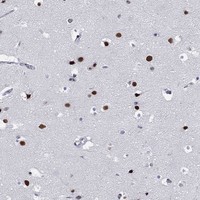

Immunohistochemical staining of human cerebral cortex shows strong nuclear positivity in neuronal cells.